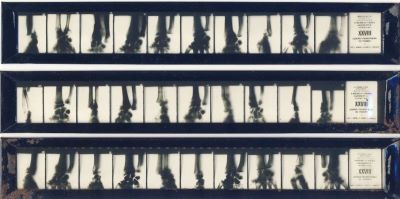

Descriere: Setul cu cele 30 de imagini radiologice, numerotate, conține aspecte ale maladiei: „Lésions traumatiques du poignet” (Leziuni traumatice ale încheieturii), Seria 28. Materialul a fost realizat de medicii Jean Quénu, G. Haret și A. Dariaux și editat sub coordonarea domnilor Henri Béclère et Pierre Porcher. Aceste filme, de dimensiuni fotografice negative obișnuite, sunt plasate în trei suporturi metalice. Fiecare ramă cuprinde câte zece roentgenograme pentru maladia prezentă; cea de-a unsprezecea imagine conține informații privind denumirea maladiei și seria. Cele trei rame cu imaginile radiologice sunt păstrate în plic original confecționat din hârtie cartonată pe care se află lipită eticheta cu toate informațiile privind setul de imagini. Imaginile radiologice sunt însoțite de un text explicativ amplu privind descrierea generală a maladiei și titlul specific fiecarei imagini radiologice. Imaginile pot fi studiate prin observare directă sau prin proiecție cu ajutorul unui aparat special denumit stereopticon.

Material/Tehnică (text): 30 de imagini radiologice ce conțin aspecte diferite ale unei maladii transpuse pe film fotografic alb-negru.